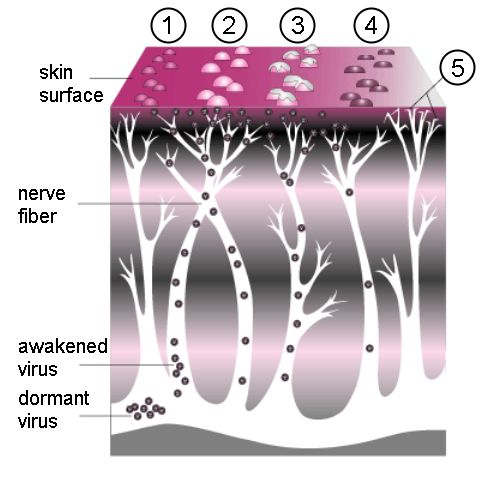

原来在治疗水痘的过程中,人体免疫系统确实把体内大多数的VZV病毒消灭掉。但仍会残留一些不能被血清中的抗体完全中和的VZV病毒。这些病毒发挥着自己天然亲近神经的特性,顺着皮肤的上皮感觉神经末梢不断逃离免疫大军攻击。最后,它们躲进了脊髓后根神经节的神经元或是颅神经的感觉神经节里,并在长期定居了下来。

不过,它们平日里就一声不吭地潜伏在那里,甚至一待可以待上几十年的光景。假设你在1-2岁得过水痘,这些病毒则会陪着你长大成人,看着你结婚生子,等待你逐渐老去。可别以为这病毒只是单纯地想跟你厮守一生,它们是在等待下一个疯狂肆虐的时机。等到你老了或者是因过度劳累,身体免疫力下降时,它们又不留情面地出来攻击你了。

据《2016 带状疱疹后神经痛诊疗中国专家共识》估计:60岁以上带状疱疹患者PHN发生率为65%,70岁以上带状疱疹患者PHN发生率为75%。当这些VZV病毒重出江湖时,它们会沿着我们的感觉神经轴突到达所支配的皮肤细胞,继而在细胞内增值引起疱疹。这样生成的疱疹沿一侧周围神经作群集带状分布。这也正是它叫做带状疱疹的原因。

与当初水痘痒得令人抓狂不同,带状疱疹是从神经发出的剧痛,分分钟让人痛不欲生。当然,这疼痛也是沿着那根受累的神经所支配的区域分布的。一些人带状疱疹只发在肋间神经的背后那段,就只有背后痛;另一些人发在面神经上,就半边脸痛。